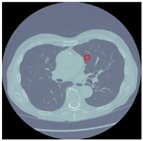

Table 12 demonstrates the results obtained from AlexNet with the SGD optimizer on the Luna16 dataset. The original image was benign, and the CNN architecture AlexNet with the SGD optimizer detected the image as benign. Next, the image was benign and AlexNet with the SGD detected the image as malignant, which was wrongly predict by AlexNet. The next image was malignant, and AlexNet with the SGD optimizer detected it as benign. Finally, the actual image was malignant, and AlexNet with the SGD optimizer detected it as malignant.

Table 12.

Detection results of AlexNet with the SGD optimizer on the LUNA16 dataset.